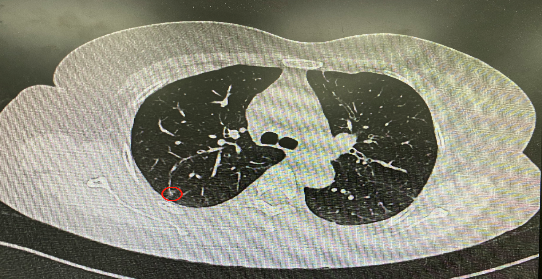

今年54歲的李女士(化名)7月初突然出現(xiàn)右上部腹痛,起初并未在意,以為稍作休息就會(huì)好轉(zhuǎn),但疼痛卻并未消退,持續(xù)了一個(gè)星期。李女士實(shí)在難以忍受,才在家人陪伴下來到西安國(guó)際醫(yī)學(xué)中心醫(yī)院就診。胸外科二病區(qū)崔凱主任接診患者后,詳細(xì)詢問病情并查閱檢查資料,經(jīng)胸部HRCT檢查,結(jié)果提示:右肺上葉后段混合密度結(jié)節(jié)影,考慮原位癌可能,即將患者收入胸腔外科二病區(qū)住院治療。

經(jīng)與患者家屬溝通,崔凱主任決定行外科手術(shù)治療。為達(dá)到精準(zhǔn)切除,術(shù)前需進(jìn)行肺小結(jié)節(jié)切除前定位。由于結(jié)節(jié)位于右肺上葉后段,傳統(tǒng)經(jīng)胸外穿刺術(shù)無法抵達(dá)病灶。崔凱主任與呼吸內(nèi)科一病區(qū)歐陽海峰主任討論后,決定擬行LungPro全肺診療導(dǎo)航下染色定位。即術(shù)前通過Lung Pro導(dǎo)航規(guī)劃染色位置,經(jīng)Lung Pro實(shí)時(shí)引導(dǎo)支氣管鏡抵達(dá)既定位置,注入亞甲藍(lán)染色劑標(biāo)記結(jié)節(jié)位置。

使用術(shù)前規(guī)劃系統(tǒng)重建全肺3D模型,并于外科醫(yī)生討論染色位置,最終確定標(biāo)記染色點(diǎn)—右肺上葉后段b亞段(RB2b)。術(shù)中使用P290(4.9mm外徑)標(biāo)準(zhǔn)支氣管鏡,根據(jù)導(dǎo)航術(shù)前規(guī)劃路徑,Lung Pro實(shí)時(shí)導(dǎo)航下,GS鞘管進(jìn)入RB2b遠(yuǎn)端官腔外病灶并注射亞甲藍(lán)染色劑。

一切準(zhǔn)備就緒,7月15日,崔凱主任團(tuán)隊(duì)聯(lián)合歐陽海峰主任團(tuán)隊(duì)為患者行單孔胸腔鏡下右肺上葉后段切除術(shù),手術(shù)用時(shí)128分鐘順利完成。進(jìn)入胸腔后,亞甲藍(lán)染色部位明顯,患者發(fā)生癌變的右肺上葉后段被成功切除。術(shù)后標(biāo)本根據(jù)染色部位迅速找到結(jié)節(jié),剖開位置兼染色位置和病灶完全符合,行術(shù)中冰凍后快速送病理檢查。經(jīng)術(shù)后病理檢查,明確診斷為(右肺上葉)原位腺癌。